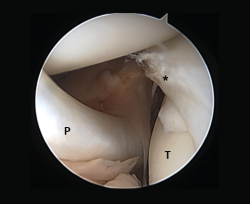

Meniscal ramp lesions

Although recently greater importance is being placed on the presence of so-called meniscal ramp lesions (Figure 3), with an estimated incidence of up to 23.9%(19) associated to ACL rupture, these lesions were already described by Strobel(20) in 1988 as a particular type of meniscal injury associated to ACL rupture and affecting the peripheral insertion of the posterior horn of the medial meniscus. These injuries are also referred to as hidden lesions of the posterior horn of the medial meniscus, since they may go undetected in the MRI studies(21). From the biomechanical perspective, ramp lesions of the knee with ACL rupture increase anterior translation of the tibia, internal and external rotation, and pivot shift. If not repaired, rotational stability following reconstruction of the ligament likewise is not fully restored(22).

[[{"fid":"4712","view_mode":"default","fields":{"format":"default","alignment":""},"type":"media","field_deltas":{"3":{"format":"default","alignment":""}},"link_text":null,"attributes":{"class":"media-element file-default","data-delta":"3"}}]]

Diagnosis

No clinical test is currently available allowing us to suspect the presence of these lesions. Magnetic resonance imaging is the diagnostic technique of choice, with the description of two signs associated to this disorder: the presence of an irregularity at the posterior margin of the medial meniscus, and the presence of joint fluid in the space between the posterior horn and the capsule(21). It has also been shown that the presence of edema in the posterior zone of the medial tibial plateau increases the probability of a meniscal ramp lesion(23). The definitive diagnosis is based on the arthroscopy findings. Authors such as Sonnery-Cottet(24) have described a systematic surgical exploration protocol to prevent such lesions from going undetected. In this exploration they recommend the use of a posteromedial port in order to allow improved visualization and even use a palpator probe to test the presence of these lesions, which are sometimes covered by a kind of membrane.